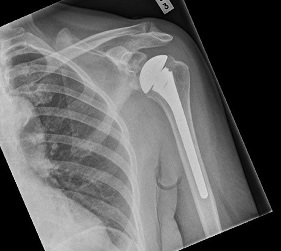

Reverse geometry total shoulder replacement: This procedure in which both the

ball and the socket are replaced and reversed, is practiced for rotator cuff

arthropathy. In the presence of a cuff tear, the deltoid is the only functioning

muscle. Reversing the normal shoulder medializes the centre of rotation of the

joint. This maximises the lever arm of the deltoid muscle and helps achieve a

better range of motion of the shoulder.